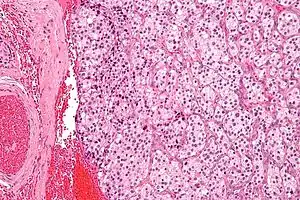

| Micrograph of a carotid body tumor (a type of paraganglioma). | |

The paragangliomas appear grossly as sharply circumscribed polypoid masses and they have a firm to rubbery consistency. They are highly vascular tumors and may have a deep red color.

On microscopic inspection, the tumor cells are readily recognized. Individual tumor cells are polygonal to oval and are arranged in distinctive cell balls, called Zellballen.[8] These cell balls are separated by fibrovascular stroma and surrounded by sustentacular cells.

By light microscopy, the differential diagnosis includes related neuroendocrine tumors, such as carcinoid tumor, neuroendocrine carcinoma, and medullary carcinoma of the thyroid.

With immunohistochemistry, the chief cells located in the cell balls are positive for chromogranin, synaptophysin, neuron specific enolase, serotonin, neurofilament and Neural cell adhesion molecule; they are S-100 protein negative. The sustentacular cells are S-100 positive and focally positive for glial fibrillary acidic protein. By histochemistry, the paraganglioma cells are argyrophilic, periodic acid Schiff negative, mucicarmine negative, and argentaffin negative.

Micrograph of a carotid body tumor